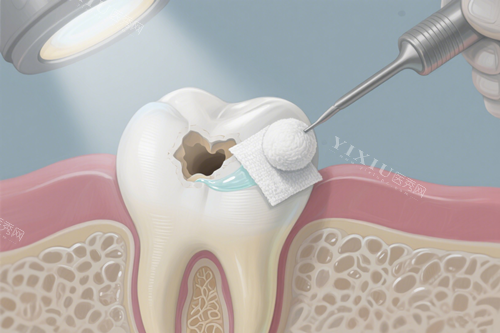

根管治疗:1000 元起

补牙:

国产树脂补牙:90 元起

美国 3M 树脂补牙:250 元起

意大利美塑(HRi)树脂补牙:351 元起

日本松风树脂补牙:146 元起

德国梅卡树脂补牙:355 元起

瑞士康特树脂补牙:316 元起

德国贺丽氏树脂补牙:274 元起